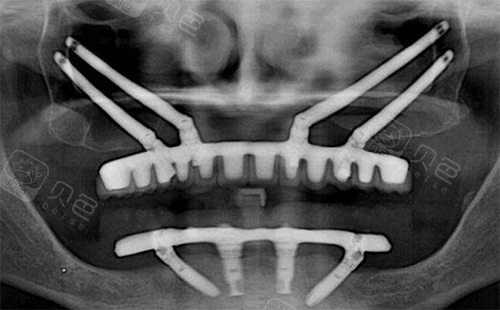

穿颧穿翼种植拍片